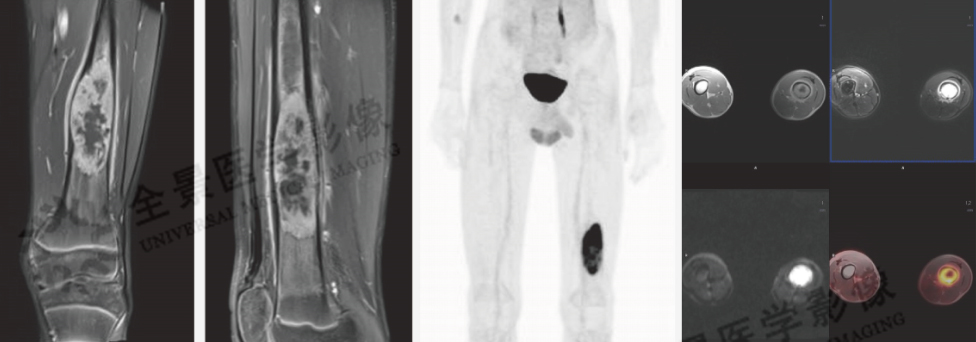

儿童肿瘤中淋巴瘤、骨骼肿瘤和软组织肿瘤均为发病率较高的病种。PET/MR所具备的低剂量和快速全身扫描特点,为儿童肿瘤的诊断发现、分期和疗效评估提供了重要价值。

案例:男童,左股骨下段痛2周,有压痛,表皮无明显红肿,MR示左股骨中下段骨质破坏,软组织肿块形成周围骨膜反应明显,增强后有强化,DWI呈高信号。PET/MR示病灶FDG明显摄取增高。

结论:考虑恶性肿瘤,随后活检病理证实为骨肉瘤。